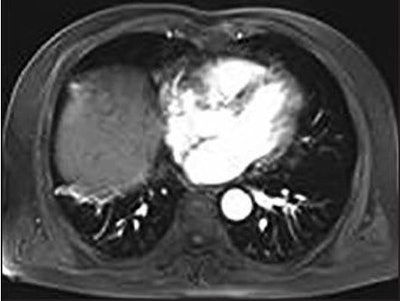

Abdominal contrast-enhanced MR image acquired three months after cryoablation procedure. No enhancement surrounds the tumor ablation zone, and the ablation zone is diminishing in size. Image courtesy of AJR.At the six-month follow-up, the researchers saw only one case (3%) of tumor progression, and all 37 patients (100%) were still alive. After one year, they saw two cases (5%) of tumor progression and one death, for a 12-month survival rate of 97%. The death was due to an upper gastrointestinal hemorrhage 10 months after cryoablation.